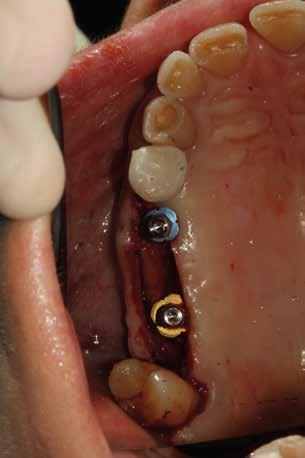

Alla visita di rivalutazione è emerso un ulteriore peggioramento della situazione, confermata anche dall’esame radiografico, con parodontopatia, sanguinamento al sondaggio, infiammazione diffusa, alitosi, difetto parodontale verticale mesiale a 2.3, residui radicolari 1.4, 1.6, 1.7, 3.6, 3.8 e carie destruenti di 1.5, 2.6, 3.5, 3.7 (con lesione endoperio) e 4.7 con estrusione e carie (Figg. 1, 2)

Il paziente, un uomo di 67 anni, ha confermato l’anamnesi precedente, ossia di essere portatore di

molteplici patologie: sindrome metabolica in discreto compenso farmacologico (riferita assunzione di metformina 500 mg, enalapril, acido acetilsalicilico, atorvastatina) e in terapia sostitutiva con levotiroxina perché operato di tiroidectomia totale per un tumore in giovane età; deambulazione autonoma con aiuto del bastone per via di un intervento al ginocchio abbastanza recente (riferito 6 mesi prima intervento di protesi totale di ginocchio).

La proposta che il paziente ha accettato è stata poi quella, previa bonifica di tutti gli elementi irrecuperabili, di riabilitare con impianti prima il 1° e 4° quadrante e in seguito il 2° e 3° e procedere poi alla protesi definitiva in un’unica soluzione.

Prima di procedere con gli interventi si è richiesto degli ematochimici di routine, per controllare soprattutto la glicemia, l’emoglobina glicata, la coagulazione, la vitamina D e i sali minerali.

Al controllo ematologico è emersa una emoglobina glicosilata molto superiore la percentuale accettabile a procedere (il valore era 9,3%) e deficit di D-25OH che è stato risolto con una terapia di ripristino con colecalciferolo 25000 U.I. Data la stretta correlazione tra emoglobina glicata e affezioni orali, è ormai routine seguire un percorso che porta alla bonifica della bocca e contestualmente, che aiuta il paziente anche con il controllo della glicemia. In prima battuta comunque, abbiamo sottoposto il paziente a una seduta orale. Per via del suo stato di salute (abbiamo stabilito per lui un rischio alto) durante ogni seduta invasiva abbiamo sempre monitorato il paziente con rilevazioni multiple dei parametri e reperendo un accesso venoso pe-

riferico. Si è eseguito la maggior parte delle estrazioni in un’unica seduta operatoria, a esclusione degli elementi 2.6 e 4.7 che sono stati mantenuti perché presentavano mobilità ma non segni di focolai infettivi attivi e che si è deciso di estrarre in un secondo momento. Il follow-up post estrattivo ha consentito anche di valutare la risposta tissutale e la guarigione degli alveoli. Non è stata sospesa la terapia con l’acido acetilsalicilico. Il PRGF è stato importante per evitare alveoliti che avrebbero rallentato la guarigione (Figg. 4-6).

Dopo tre mesi dalla prima fase estrattiva sono stati ripetuti gli esami ematochimici dai quali l’emoglobina glicata del paziente è scesa a 7.2%. Abbiamo pertanto avviato con lo studio pre-implantare che prevede la ceratura diagnostica e gli esami radiologici più avanzati per scegliere i giusti impianti e la loro sede corretta.

L’esame CBCT ha rivelato un quantitativo di osseo sufficiente a procedere con l’intervento implantare, anche se erano ancora visibili le zone delle estrazioni; inoltre ha evidenziato una lesione osteolitica a carico del 3.5 che abbiamo dunque deciso di estrarre (Figg. 7-20).